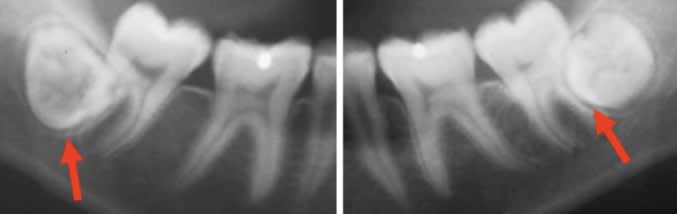

Bah alors ! Ben bien entendu qu’il faut les laisser en place ! Ça ne cause aucun problème...

il n'est pas question de ne jamais enlever les DDS mais de là à systématiquement les faire enlever suite à un traitement d'ortho parce que ça aurait une influence sur la pérénité du résultat, il y a un monde. je n'ai pas les photos mais je pourrais aussi te prouver que l'encombrement incisif se remet en place malgré l'exo des sagesses dans de nombreux cas, le rfuter serait méconnaitre l'évolution d'une bouche

Si bien sur que les dds peuvent faire en sorte que les incisives se croisent .

Non pas par la poussee ou un manque de place mais par la creation d une interference .

Et encore que ce n est meme pas forcement pas la dds qui est en cause toute seule , mais a cause du recouvrement incisif a la con et le nivellement cree par l ortho que la dds devient interferente .

Et je suis désolé mais dans un grand nombre de cas l’espace pour les DDS est très limite , voir insuffisante > caries , zone difficile à nettoyer, pericoronarite.